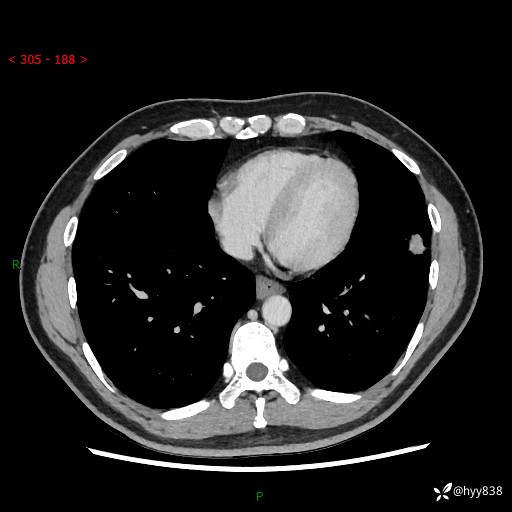

现病史:患者3月前出现胸闷,卧位时加重,坐位时缓解,无咽痛、咳嗽,无头痛,无全身酸痛,无结膜充血,无胸痛、心慌,无咯血,无呼吸困难,无咳痰,2024-07-02于当地市第一民医院行胸部CT,结果不详,2024-07-05就诊于我院急诊内科,行胸部CT同时增强,结果示:左肺下叶多发结节灶,考虑感染可能。今患者为求进一步诊治来我院,门诊以“肺部感染”收入我科。 患者本次起病来精神、食欲、睡眠尚可,大小便可,体力,体重无明显变化。

胸部CT平扫+增强

各期CT值:30hu 90hu 77hu